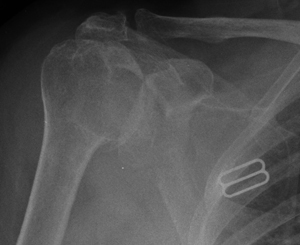

This patient never knew that the fracture he sustained 20 ago had malunited badly, until he developed shoulder pain. Corrective osteotomy with bone grafting and plate fixation carried out.

Corrective osteotomy Corrective osteotomy